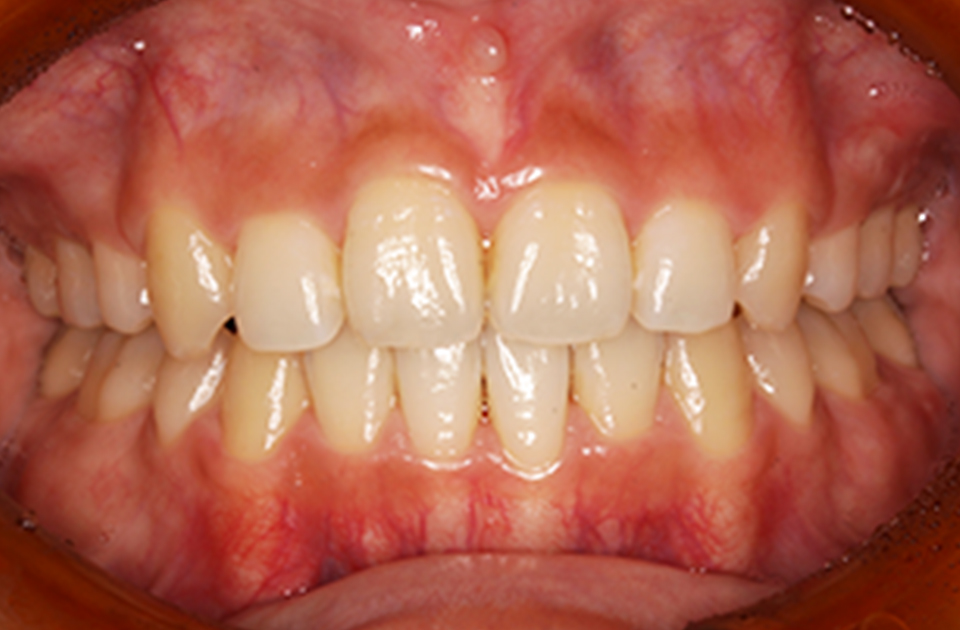

矯正前 正面

矯正後 正面

主訴 前歯で物が咬めない、歯並びの凸凹、出っ歯を治したい

治療法 上下顎マルチブラケット装置、歯科矯正用アンカースクリュー

抜歯の有無 上顎左右側第一小臼歯、下顎左右側第二小臼歯

治療期間 1年10ヶ月